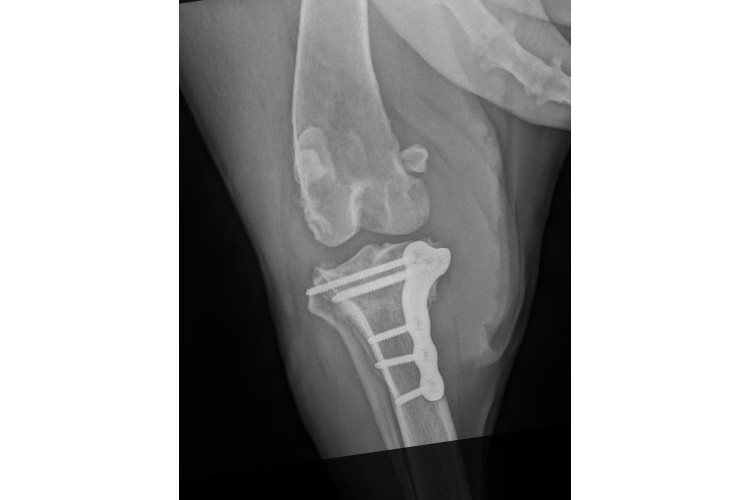

Our expertise extends to orthopaedic surgery including cruciate ligament repair and fractures. We have fixed price orthopaedic surgery packages in the interest of being as transparent as possible; the price you are quoted is the price you pay. All the packages include pre and 6 week post-operative x-rays, anaesthesia, surgery, implants, intra and post operative medication and overnight hospitalisation in our dedicated in-patient ward. Packages available are as follows:

- Fracture Repair - Level 1 - Pins/Wires - £3,400

- Fracture Repair - Level 2 - Plates/Screws - £3,800

- Fracture Repair - Level 3 - Pelvis/ Double Plate - £4,800

- Fracture Repair - Elbow - £3,600